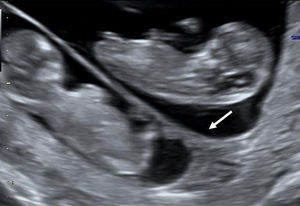

The visualization of a single chorionic sac at 4–5 weeks, however, does not exclude the possibility of a monochorionic twin pregnancy. By the sixth postmenstrual week the yolk sac and the embryo can be visualized inside the chorionic sac and the definitive diagnosis of a single pregnancy or monochorionic twin pregnancy can be done. If a single chorionic sac is visualized containing two yolk sacs and two embryonic poles, then a monochorionic twin pregnancy can be diagnosed (Fig. 2).